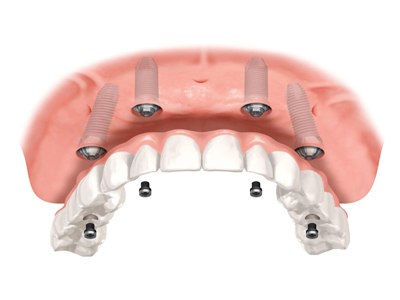

Dental Implant

Dental implant are one of the most important advancements in dentistry, offering a modern day solution for missing teeth. They are small cylindrical titanium fixtures that replace missing tooth roots and they provide a stable base for replacement teeth that feel, function, and look like natural teeth.

Dental implant can replace a single tooth, several teeth, provide retention to your denture or can completely replace your denture.